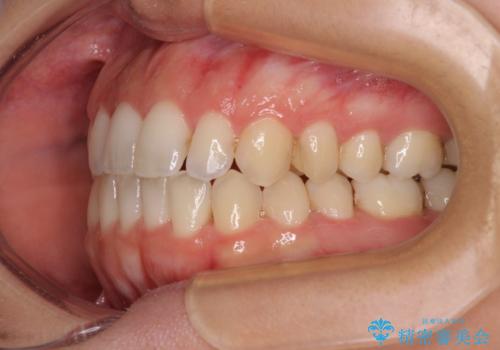

【モニター】オープンバイトをインビザライン矯正で治す

- 前歯の開咬を気にして来院された患者様です。

開咬の治療は、前歯を閉じるように動かすとともに、上下臼歯を圧下(骨内にめり込ませる)させることで進めて行きます。

インビザラインは臼歯の圧下を効果的に行えるため、インビザラインを用いて矯正治療を行うこととしました。

オープンバイトは舌の突出癖により誘発され、治療後も突出癖が残っている容易に後戻りしてしまいます。

治療期間を短縮するためにも、舌突出癖の改善が極めて重要となります。